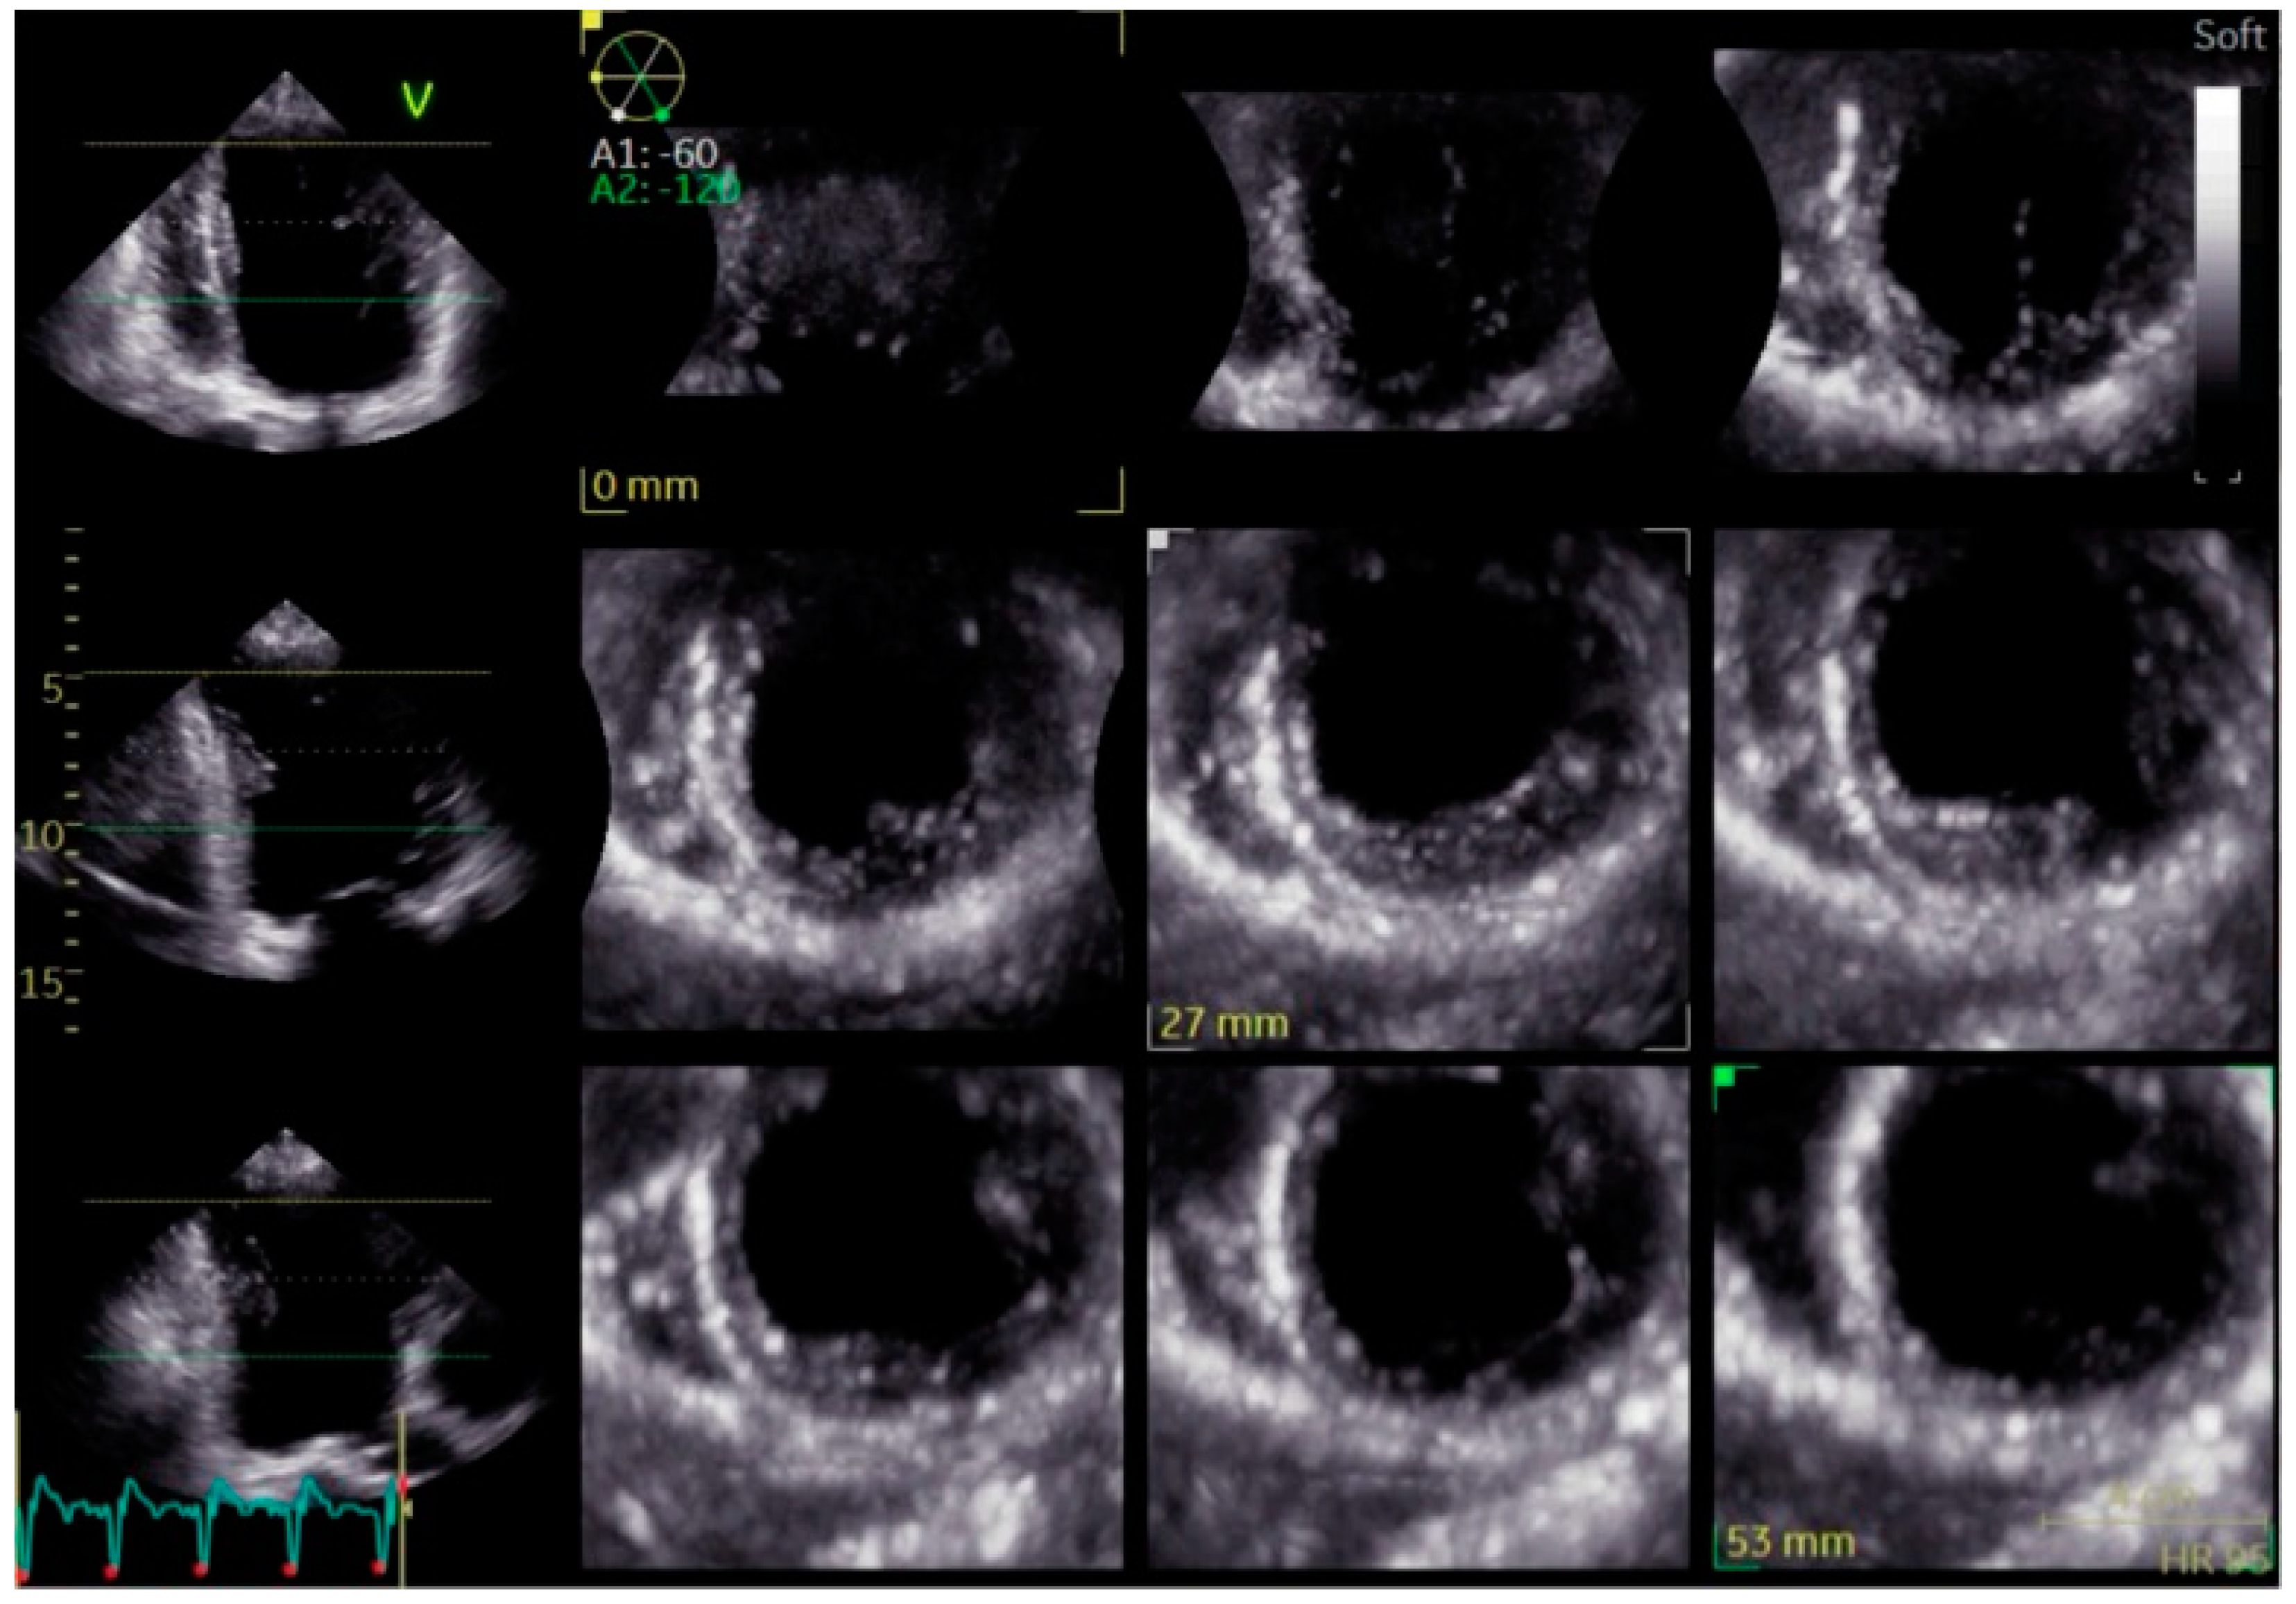

Three-Dimensional Echocardiography (3D Echo): Three-dimensional echocardiography provides an advanced volumetric analysis of ventricular mechanics, offering a more comprehensive evaluation of dyssynchrony than conventional two-dimensional methods (Figure 7). Unlike standard echocardiography, 3D imaging captures time-to-peak contraction across multiple myocardial segments, allowing for a more detailed assessment of intraventricular coordination.

In LBBB, 3D echocardiography reveals the extent of mechanical dyssynchrony and its impact on ventricular geometry and volumes. This modality is particularly useful for tracking the effects of BBP or CRT, as it can detect subtle changes in ventricular function and remodeling over time. While its availability and expertise requirements currently limit widespread use, 3D Echo is expected to play an increasing role in dyssynchrony assessment and resynchronization therapy optimization.

Figure 7. Transthoracic echocardiography showing short-axis views of the left ventricle at different levels. The images highlight increased echogenicity of the interventricular septum, suggestive of septal fibrosis, which may indicate myocardial remodeling.